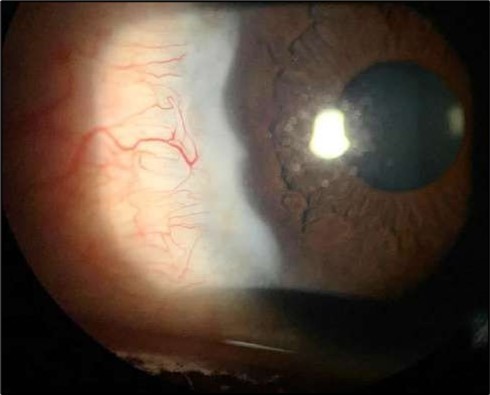

Two weeks post-surgery, the left eye showed significant healing, with a small conjunctival granuloma and vascularization at the ulcer margins. The cornea was clear with a central leading edge nasally, deep and quiet anterior chamber and clear lens. VA 6/6 bilaterally and IOP normal. Histopathology of excised conjunctiva showed non-keratinized squamous epithelium with superficial erosions, stromal elastosis, hemorrhage, and inflammatory infiltration, but no signs of granulomatous disease, malignancy, or viral evidence, findings consistent with idiopathic localized inflammatory process. The patient reported significant relief and satisfaction post-surgery, resuming normal activities. Treatment continued with oral prednisolone 25 milligrams every other day, tobramycin-dexamethasone ointment twice daily, and preservative-free artificial tears four times daily Figure 4, Figure 5a, Figure 5b, Figure 5c, Figure 5d.

Figure 4.OS. Slit-lamp photograph showing a partially quiet ocular surface two weeks following surgical excision of adjacent perilimbal conjunctiva.

OS. Slit-lamp photograph showing a partially quiet ocular surface two weeks following surgical excision of adjacent perilimbal conjunctiva.

At six-months follow-up post-resection, the ulcer showed progressive epithelialization with no recurrence. Oral prednisolone was gradually tapered and stopped. The patient remains under regular ophthalmology follow-up with stable ocular findings Figure 6.

Figure 6.Six-month follow-up image showing a stable ocular surface, and absence of ulcer recurrence. The cornea appears clear centrally, with stromal scarring limited to the periphery.

Six-month follow-up image showing a stable ocular surface, and absence of ulcer recurrence. The cornea appears clear centrally, with stromal scarring limited to the periphery.